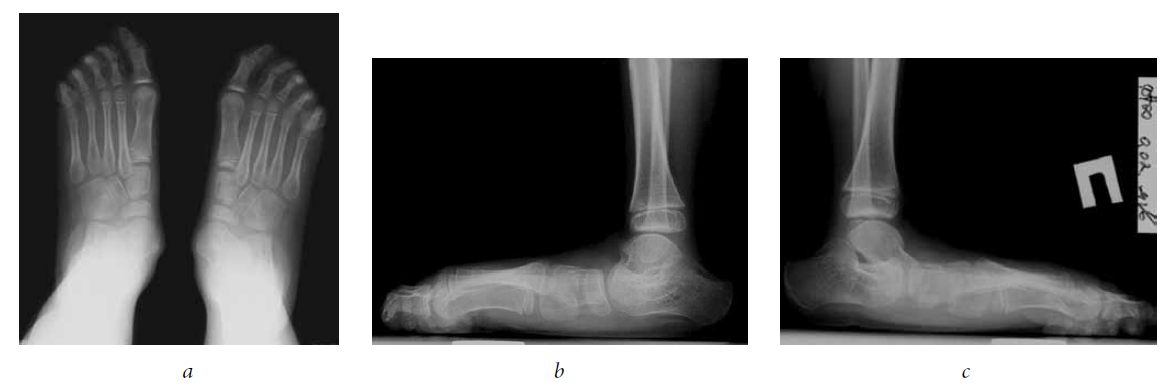

The surgery to eliminate TEPV was performed (Strayer surgery, subtalar arthroereisis, transposition with tenodesis of the anterior tibial muscle tendon under the navicular bone, grafting of the capsule of the talo-navicular joint). A cylinder plaster cast was applied from the upper third of the thigh to the tips of the toes. After 2 weeks, vertical orientation with a partial load in a plaster cast was allowed, 4 weeks after the plaster cast was removed, and a rehabilitation course was started. After 2 years and 6 months, the subtalar implants were removed (Fig. 3, 4).

Fig. 3. Radiographs of the feet under load 2 years and 6 months after surgery (lateral views)